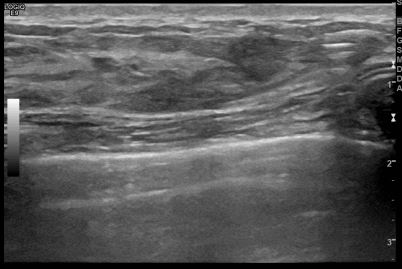

상기환자는 외부검사이상소견으로  내원하신 40대후반

여성분으로 의심스러운 우측혹 조직검사 시행해 침윤성암 으로 진단되었습니다